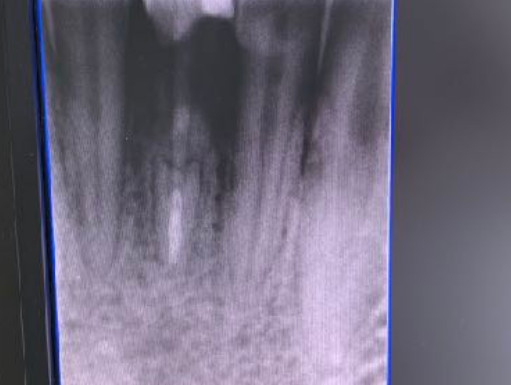

L’osso anteriore della mandibola è notoriamente un osso robusto adatto a sopportare carichi masticatori importanti. Le valutazioni preimplantari prevedono esame TAC cone beam presso il ns ambulatorio di Acquafredda, per i casi più complessi. In ogni caso si valuta con la palpazione andamento, altezza, spessore e inclinazione dell’osso, tenendo presente la classe dentale è la eventuale versione linguale dei denti anteriori. Durante l’inserimento si valuta invece la densità mentre la fresa lanceolata si affonda a bassa velocità.

La codifica della densità è quella adottata da Carl Misch e va da un massimo di D1 ad un minimo di D5 per l’osso meno consistente.Il valore della densità trova conferma nel torque presente al momento della maschiatura. Con valori di torque elevato è opportuno scegliere maschiatore ed impianto di diametro minori, ad esempio diametro 4 mm. Con valori di torque via via più basso è opportuno aumentare il diametro dell’impianto compatibilmente con lo spessore tra le corticali. Ricordo che a differenza di sistematiche implantari correnti il valore del collo emergente dell’impianto di Tramonte è sempre e soltanto di mm 2 anche quando il diametro complessivo è di mm 6 o 7 o addirittura mm 8 o 10.

Il diametro ridotto del collo consente di mettersi al riparo da eventuali periimplantiti e migliora nettamente la velocità della guarigione. In questo caso è stato maschiato con un diametro 4 ed è stato inserito un impianto di Tramonte diametro 4 mm a 7 spire a collo corto . Il titanio utilizzato è sempre di grado 4.

| App. Rx endorale: rx Vix-Win Guidizzolo | TAC: no |

| Situazione estrattiva: Impianto postestrattivo immediato a carico immediato. | Densità secondo Misch: D2 |